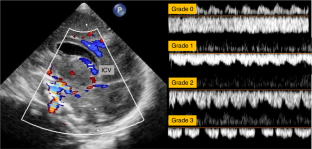

Ikeda, T. et al. Changes in the perfusion waveform of the internal cerebral vein and intraventricular hemorrhage in the acute management of extremely low-birth-weight infants. Eur. J. Pediatr. 174, 331–338 (2015).

Tanaka, K. et al. Changes in Internal Cerebral Vein Pulsation and Intraventricular Hemorrhage in Extremely Preterm Infants. Am. J. Perinatol. 41, e37–e45 (2024).